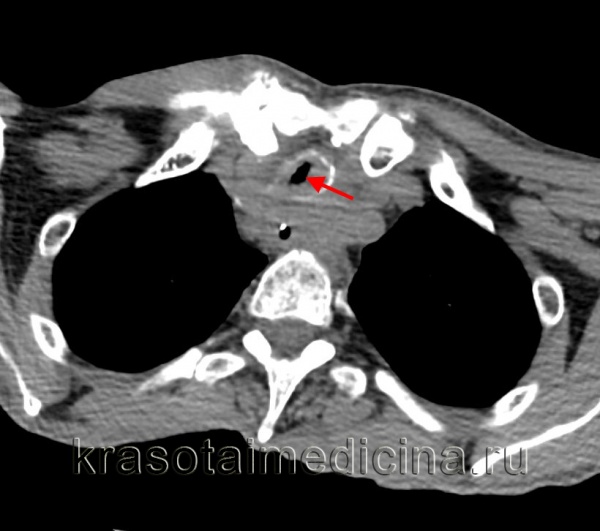

![КТ органов грудной клетки. Выраженный стеноз проксимальных отделов трахеи вследствие вторичного распространения опухоли гортани]()

КТ органов грудной клетки. Выраженный стеноз проксимальных отделов трахеи вследствие вторичного распространения опухоли гортани